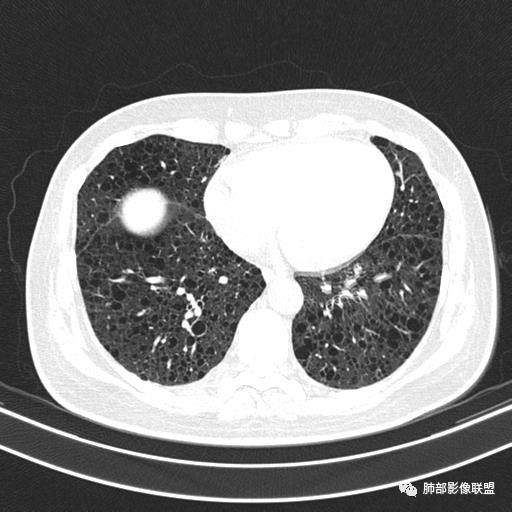

中年女性,不吸烟

双肺弥漫囊腔,累及肋膈角,囊腔形态相对规则单一。

CT平扫示双肺弥漫分布大小不等囊状薄壁透光区,无内、中、外带分布差异,间质稍示增厚。拟LAM

我也支持刘老师。中年女性,咳嗽气喘,有苯吸入史,双肺野多发囊腔,囊腔形态相对规则,大小不一,壁薄,有的似无壁,双肺弥漫磨玻璃影,有间质性改变,育龄期女性,首选考虑lam,但是患者有吸入苯病史半年,囊腔形态不是很规则,大小不一,分布不均匀,有的无壁似小叶中央肺气肿,有弥漫性磨玻璃及间质性改变,不排除吸入引起的间质性肺炎?

中年女性,双肺弥漫性磨玻璃密度影,并见弥漫性分布大小不一囊腔,壁薄,形态规则,考虑lam,鉴别苯中毒肺损伤致间质改变

中年女性育龄期妇女,咳嗽气喘,无吸烟史,有苯吸入史。影像:双肺弥漫均匀小囊腔,无明显分布优势,囊腔形态欠规则,壁薄,部分囊腔边缘血管征,伴双肺弥漫磨玻璃影,无结节,考虑lam,鉴别苯中毒肺损伤,囊腔多有分布优势,小叶中心分布为主,形态规整等

中年女性,两肺弥漫分布囊性低密度影,壁薄,相对规则,境界尚清晰,考虑LAM

中年育龄期女性,双肺多发含气囊腔弥漫性分布,囊间肺组织结构正常,常规考虑Lam

女,46,活动性气喘1年。苯吸入史半年。胸部CT:两肺弥漫囊腔,上至肺尖,下至肋膈角,形态类似小囊腔。考虑:LAM,鉴别LIP,BHD,PLCH等。

双肺弥漫大小不一薄壁含气囊腔,囊间肺组织正常,正常肺背景,肺尖肺底受累;青年女性,气喘,支持LAM

双肺多发大小相近的囊状影,分布趋势趋于一致,中年女性,考虑LAM。部分囊内见血管及分隔影,小叶中心性肺气肿代排

CT表现:双肺弥漫大小不等的薄壁囊腔,囊壁<2mm,外形规则,血管影多位于囊腔周围,囊腔之间肺组织正常,随着疾病进展到晚期,囊腔变大、增多,不可胜数,囊腔可融合成较大的囊,与肺气肿相似,形成间质性肺纤维化。部分病例可出现结节影。

1.小叶中心性肺气肿:上肺为主,无壁,中央见小血管影,位于小叶核心周围,部分血管可推移到边缘,周围肺组织正常

CT表现:早期阶段以结节为主,小结节分布于小叶内、支气管血管束旁及小叶间隔,囊腔形态不规则,呈分支状、两叶或三叶,大小不一,囊壁厚薄不均,主要以中上肺受累为主,双侧肋膈角往往不受累,终末期过度充气及广泛囊腔形成网状纤维化或终末肺气肿,也可导致自发性气胸。